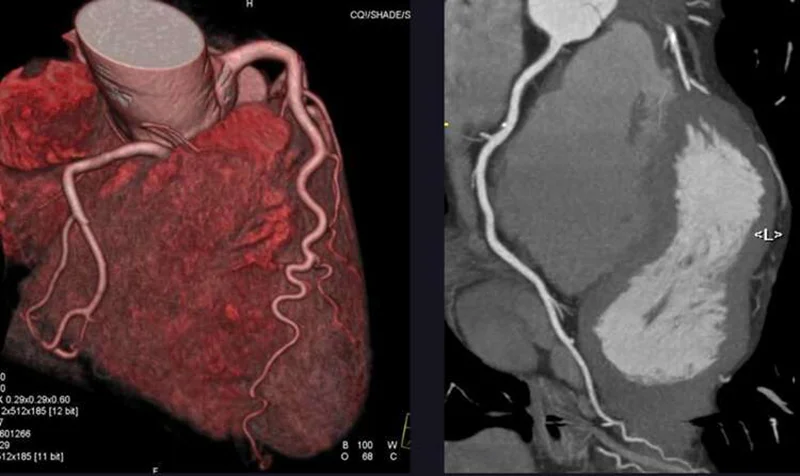

Over the past 20 years, coronary computed tomographic angiography (CCTA) has emerged as another noninvasive method for diagnosing obstructive CAD. Among patients with intermediate or high pretest probability of obstructive CAD, CCTA has been found to have a sensitivity, specificity, positive predictive value, and negative predictive value for identifying obstructive CAD of 0.92, 0.75, 0.84, and 0.87, respectively.5 On the basis of these data and the results of five randomized, controlled trials conducted over the past 10 years, CCTA has become the preferred imaging approach for the assessment of patients with stable chest pain, especially in those with an intermediate pretest probability of obstructive CAD.

The members of the DISCHARGE Trial Group now report in the Journalthe results of a pragmatic, randomized trial of CCTA as compared with angiography as an initial diagnostic imaging strategy in 3561 patients with stable chest pain and an intermediate pretest probability of obstructive CAD. The authors found no material difference between CCTA and angiography in the incidence of the primary composite outcome of cardiovascular death, nonfatal myocardial infarction, or nonfatal stroke during 3.5 years of follow-up. This result is probably a consequence of the lack of effect of revascularization on cardiovascular events among most patients with stable angina and the limited number of those with high-risk anatomy who would benefit from revascularization in the trial (13.9% in the CCTA group and 11.2% in the angiography group). In addition, CCTA was performed significantly earlier than angiography (3 days vs. 12 days after enrollment), which may have led to earlier revascularization and a better outcome in patients whose anatomy would benefit from it.